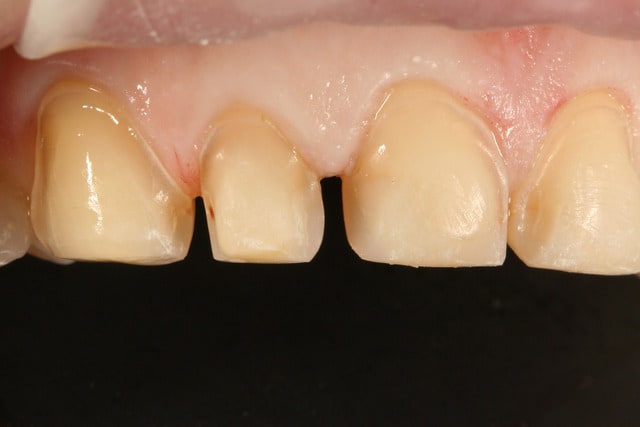

pour les points de caries que j'ai découverts entre 22 et 23, j'ai essayé d'en enlever un maximum en préparant, mais c'est vrai qu'en regardant les photos ça semble un peu limite sur la 22, peut être que j'y repasserait un coup de fraise avant de coller les facettes.

par contre j'ai plus peur du risque de carie derrière la facette effectivement, j'aurais du creuser un peu plus et mettre un peu de compo

oui, je me suis fait la même remarque en voyant les photos, j'ai fait ça en allant chercher la zone cariée et j'espère que le fait que ce soit de l'emax et pas de la feldspathique pure compensera mon erreur